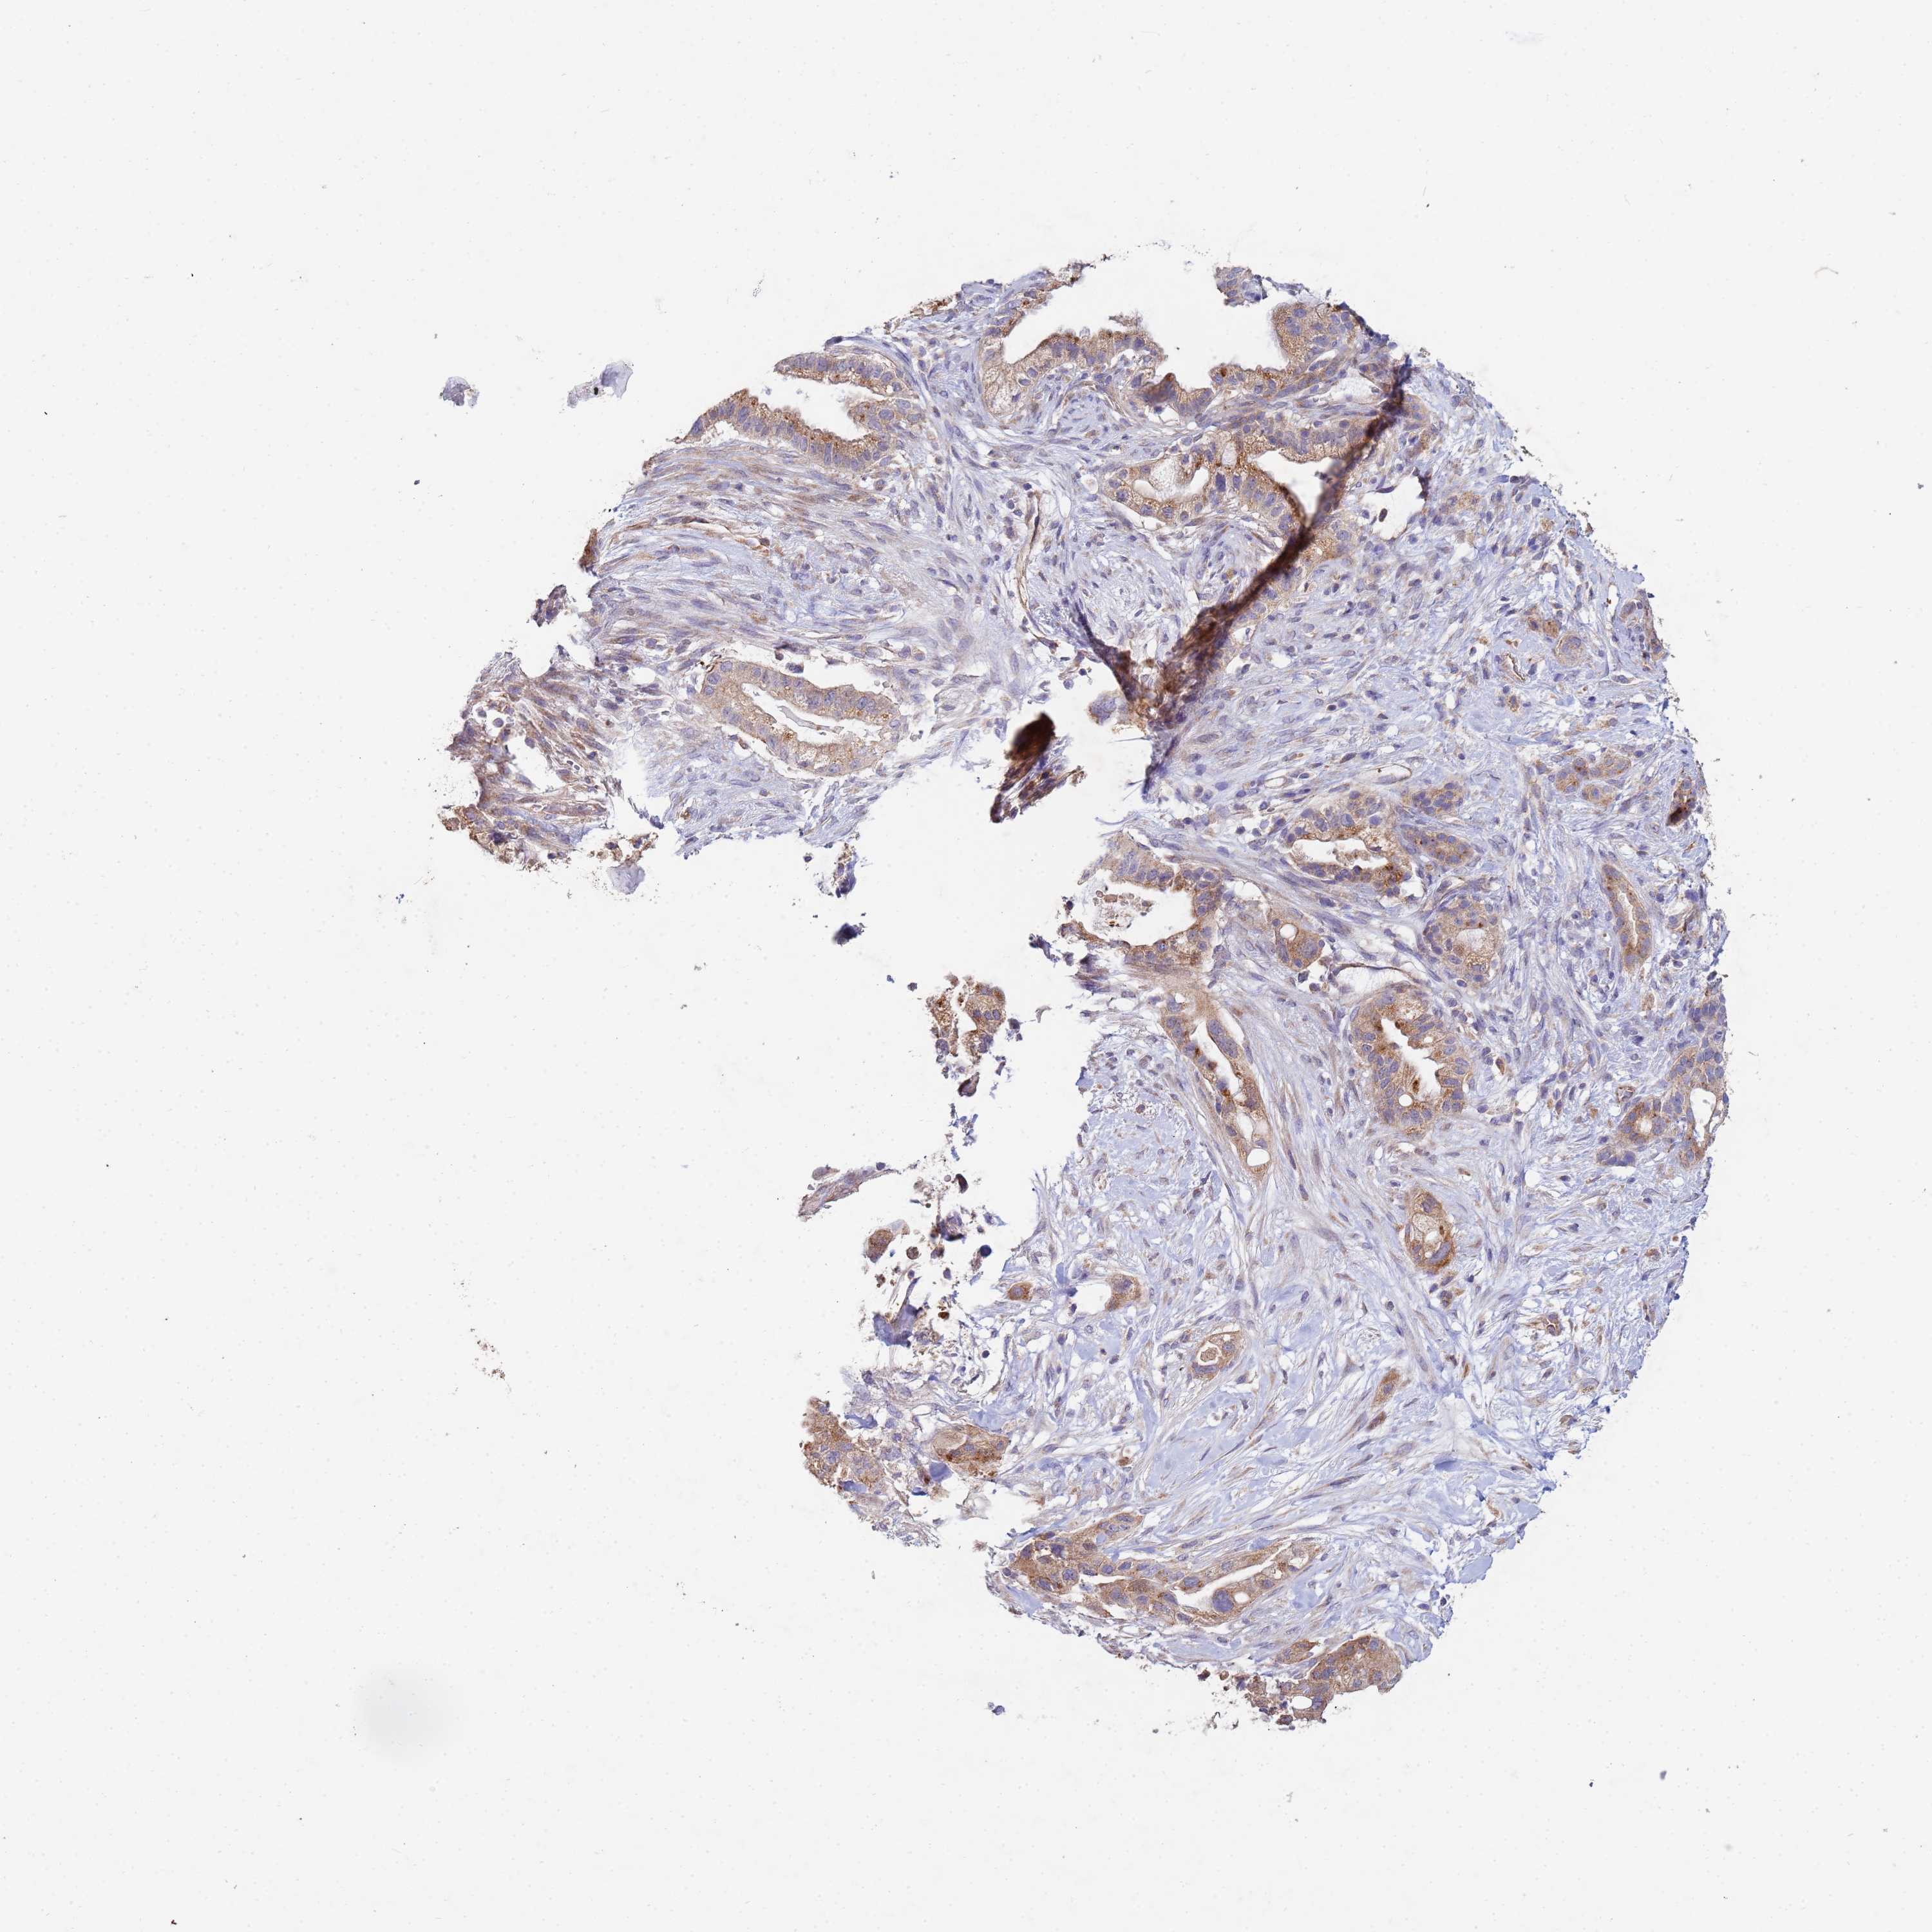

PANCREATIC CANCER - Protein expressioni

A mouse-over function shows sample information and annotation data. Click on an image to view it in a full screen mode. Samples can be filtered based on level of antibody staining by selecting one or several of the following categories: high, medium, low and not detected. The assay and annotation is described here.

Note that samples used for immunohistochemistry by the Human Protein Atlas do not correspond to samples in the TCGA dataset.

Antibody stainingi

Antibody staining in the annotated cell types in the current human tissue is reported as not detected, low, medium, or high, based on conventional immunohistochemistry profiling in selected tissues. This score is based on the combination of the staining intensity and fraction of stained cells.

Each image is clickable and will lead to virtual microscopy that enables deeper exploration of all samples and also displays staining intensity scores, fraction scores and subcellular localization as well as patient and tissue information for each sample.

Antibody HPA002382

Antibody CAB005109

Antibody CAB047311

Staining

High

Medium

Low

Not detected

Intensity

Strong

Moderate

Weak

Negative

Quantity

>75%

75%-25%

<25%

None

Location

Nuclear

Cytoplasmic/membranous

Cytoplasmic/membranous,nuclear

Adenocarcinoma, NOS

Adenocarcinoma, metastatic, NOS